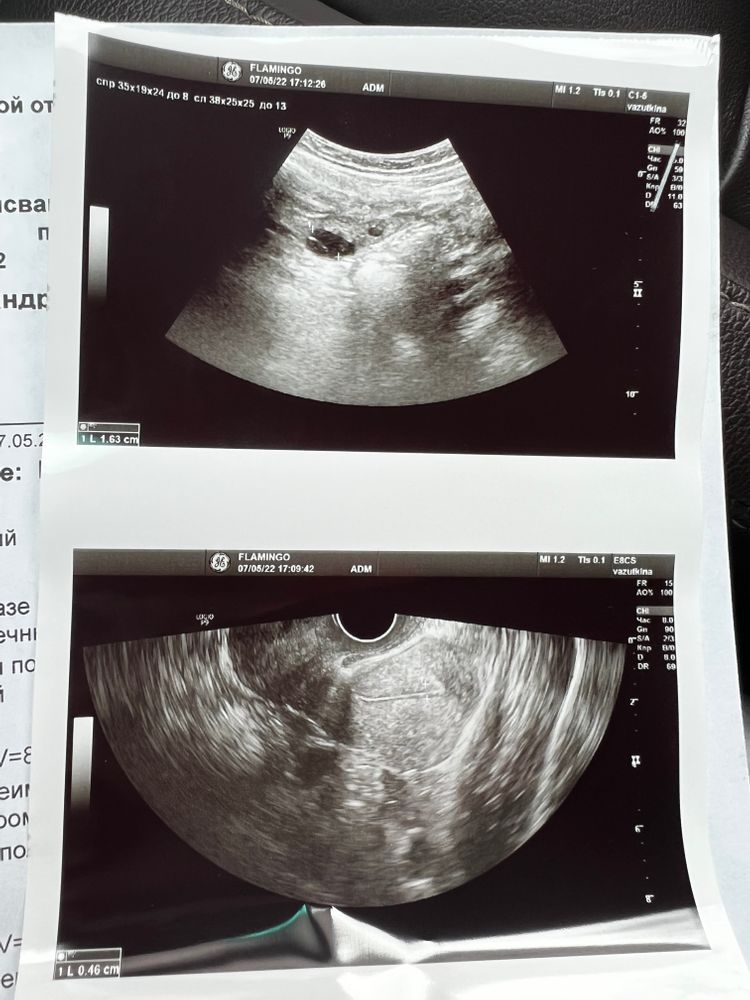

7 ДЦ, 3 день стимуляции - Узи

Стимуляция3 день стимуляции, сходила на узи. В итоге на 7 день цикла у меня в левом яичнике один фолликул 16 мм, другой 13. Ничего себе)

у кого был такой стремительный рост? Доза 75 , сделала пока два укола